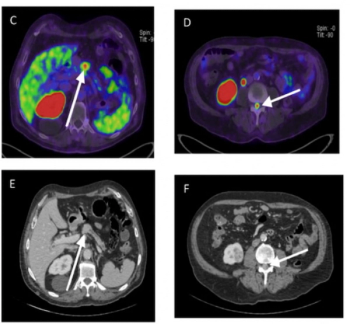

Sixty-five percent of patients with newly diagnosed high-risk prostate cancer may have extraprostatic extension on MRI, and PSMA PET/CT findings suggest those with Gleason scores of eight or higher have more than double the risk of metastasis, according to a new study presented at the European Congress of Radiology (ECR).